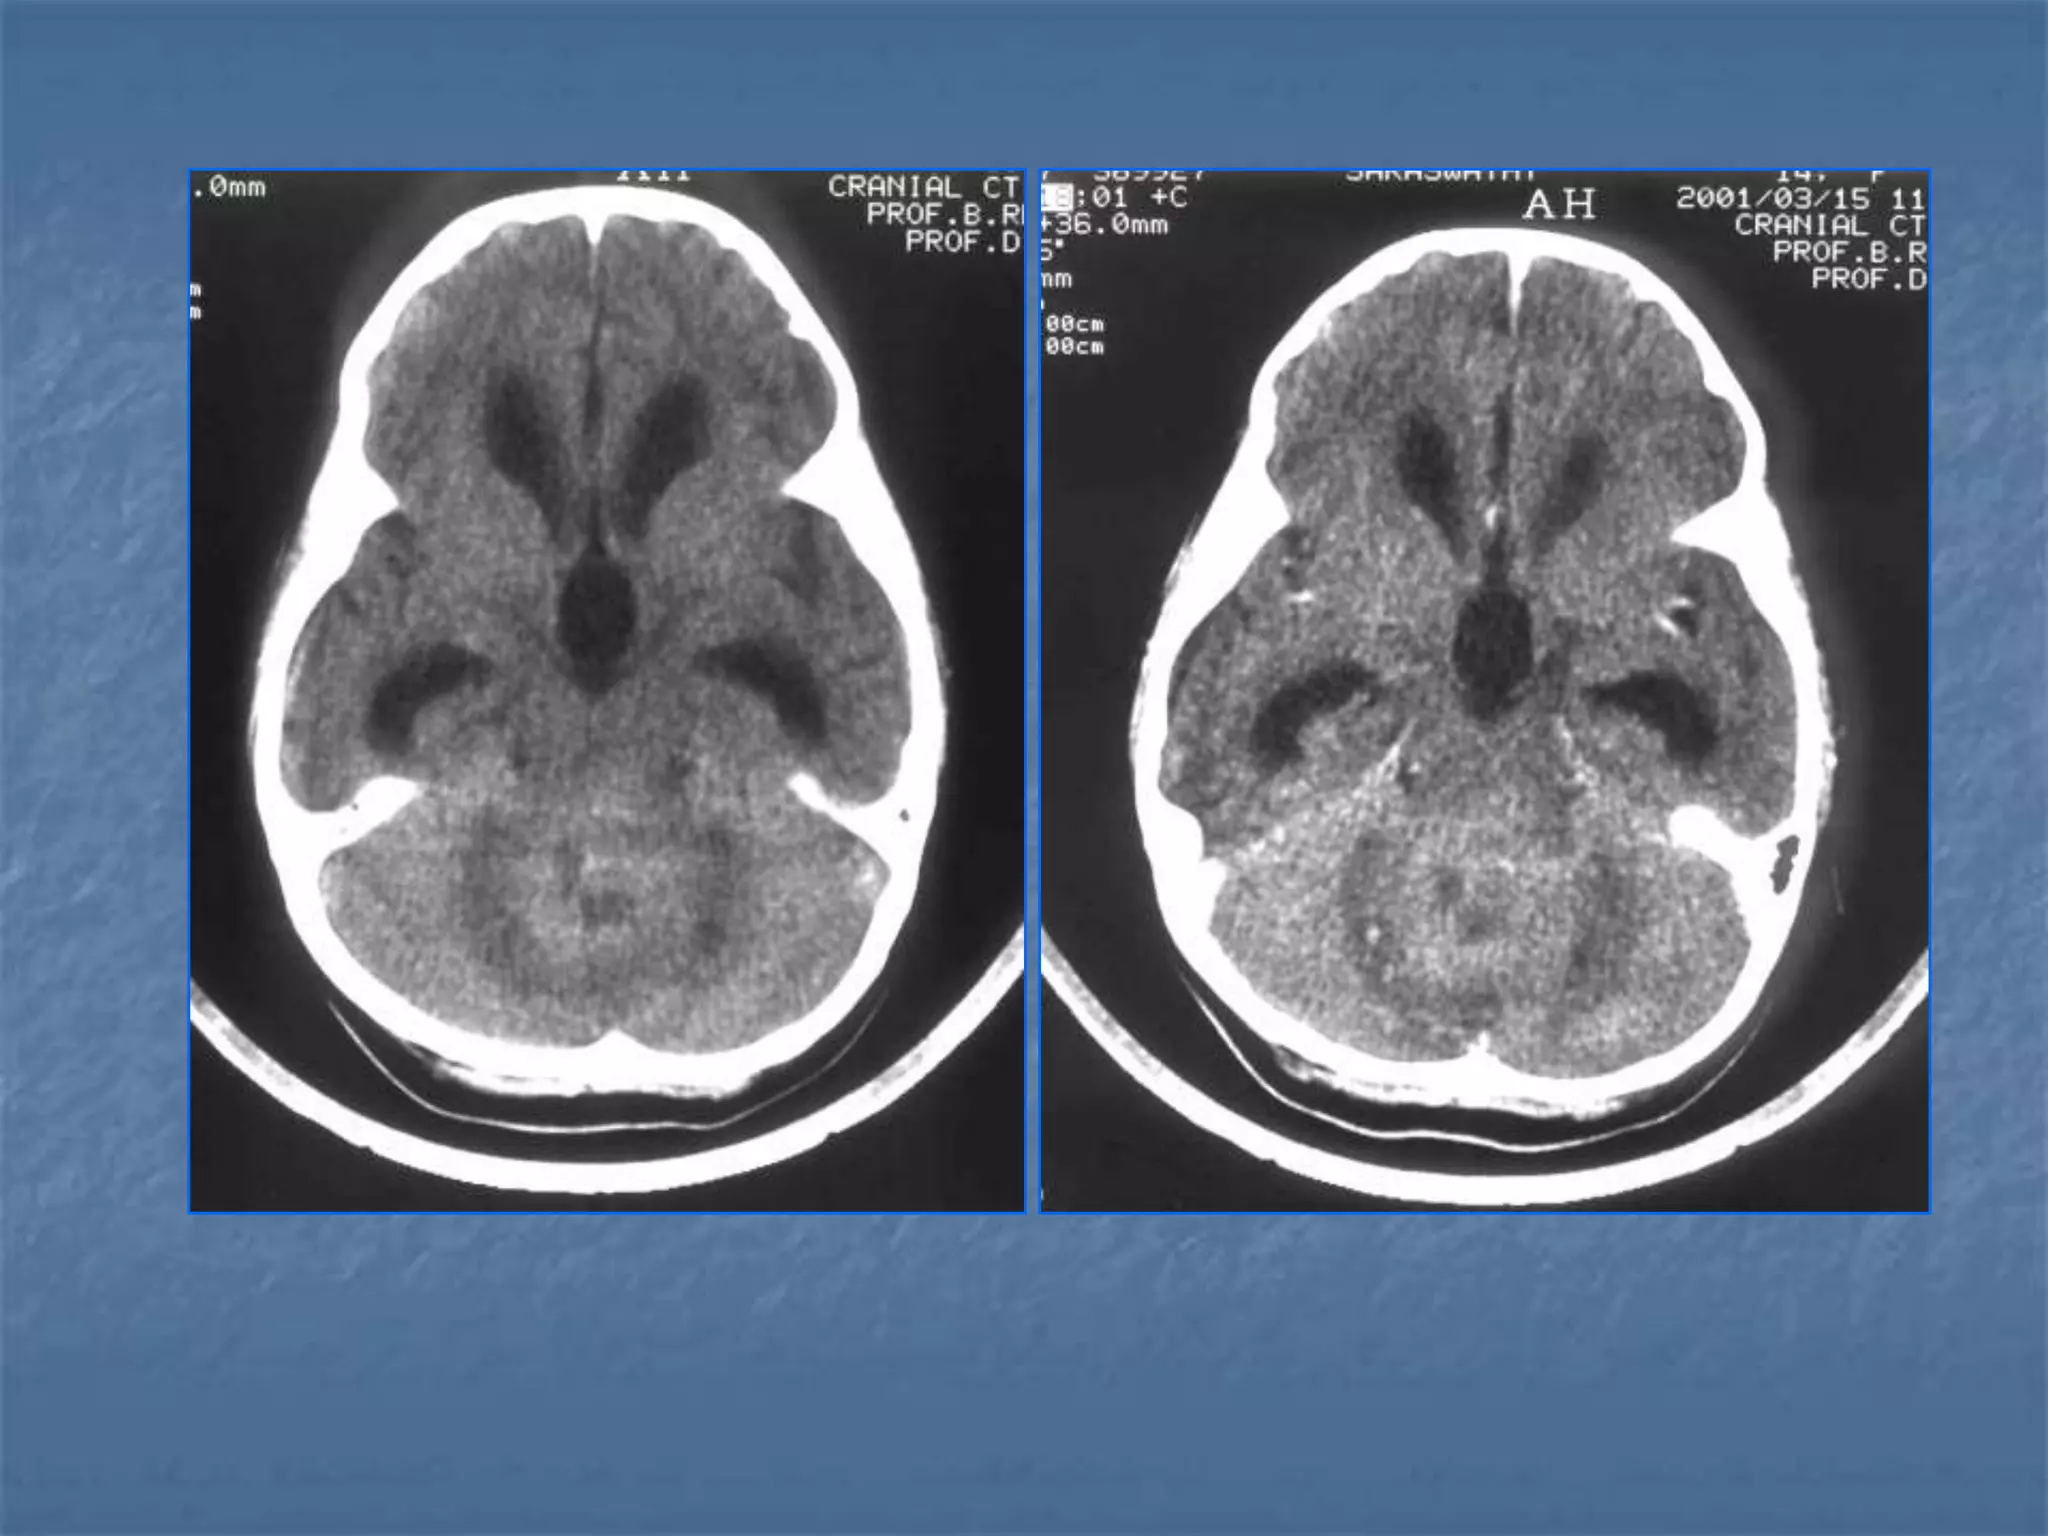

Hypertensive Hemorrhage

 Hypertensive hemorrhage accounts for

approximately 70-90% of non-traumatic primary

intracerebral hemorrhages. It is commonly due to

vasculopathy involving deep penetrating arteries

of the brain. Hypertensive hemorrhage has a

predilection for deep structures including the

thalamus, pons, cerebellum, and basal ganglia,

particularly the putamen and external capsule.

Thus, it often appears as a high-density

hemorrhage in the region of the basal ganglia.

Blood may extend into the ventricular system.

Intraventricular extension of the hematoma is

associated with a poor prognosis.

Haemorrhagic StrokeEtiology

 Hemorrhages can occur in the intraparenchymal,

subarachnoid, intraventricular, subdural and

extradural spaces.

 Location of hypertensive hemorrhage:

Putamen, external capsule, thalamus, pons,

cerebellum, subcortical white matter

Subarachnoid hemorrhage

 In the absence of trauma, the most common cause

of subarachnoid hemorrhage is a ruptured cerebral

aneurysm. Cerebral aneurysms tend to occur at

branch points of intracranial vessels and thus are

frequently located around the Circle of Willis.

Common aneurysm locations include the anterior

and posterior communicating arteries, the middle

cerebral artery bifurcation and the tip of the basilar

artery. Subarachnoid hemorrhage typically presents

as the "worst headache of life" for the patient.

Detection of a subarachnoid hemorrhage is crucial

because the rehemorrhage rate of ruptured

aneurysms is high and rehemorrhage is often fatal.

 CT is currently the imaging modality of choice because

of its high sensitivity for the detection of subarachnoid

hemorrhage. CT is most sensitive for acute

subarachnoid hemorrhage. After a period of days to

weeks CT becomes much less sensitive as blood is

resorbed from the CSF. If there is a strong clinical

indication, LP may be warranted despite a negative CT

since small bleeds can be unapparent on imaging.

On CT, a subarachnoid hemorrhage appears as high

density within sulci and cisterns. The insular regions

and basilar cisterns should be carefully scrutinized for

subtle signs of subarachnoid hemorrhage.

Subarachnoid hemorrhage may have associated

intraventricular hemorrhage and hydrocephalus.